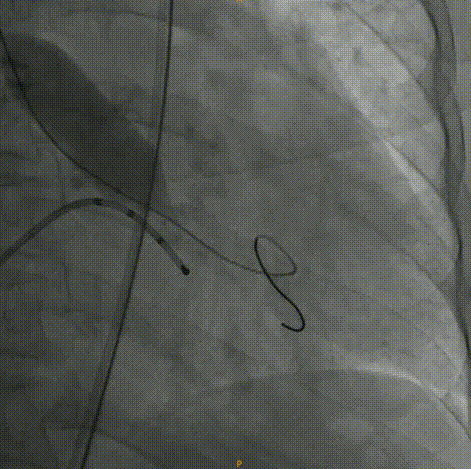

Venus26号瓣膜释放:位置良好,轻度反流,遂完全释放后采取后扩。

后扩后瓣膜最终形态。